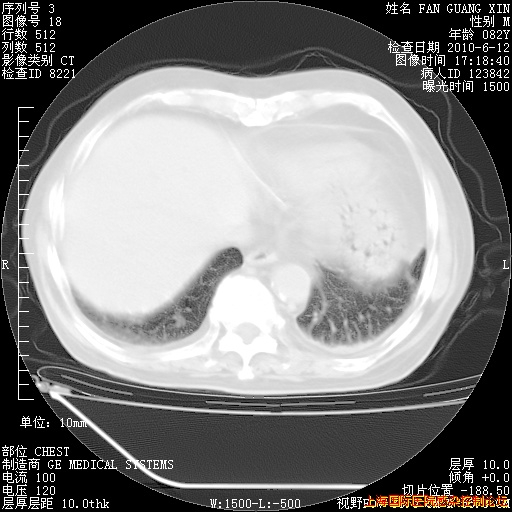

6月12日纵膈窗

整整相隔30天的肺部CT好像有所好转啊。甲强龙减量第3天,需要观察体温。

海管,自昨日你和我通完话后,不知您岳父消化道症状有无缓解?体温怎样?阅读7.12日胸部ct,个人认为目前激素治疗是有效的,甲强龙减量是适宜的。因在抗痨治疗,需密切观察肝功、肾功能和血常规。不过,老年、长期住院和大量使用激素,很担心菌群失调发生